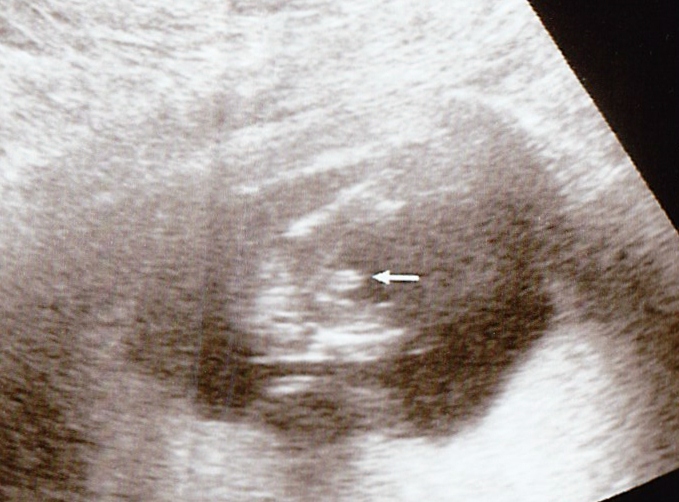

Ok, had a quick scan at 15w0d to peek at gender. She first said girl for a while, then changed her mind half way through the scan. I see its obviously protruding, but the 3 lines are making me crazy! What do you think? :suprise:

Attachment 8634Attachment 8635Attachment 8636